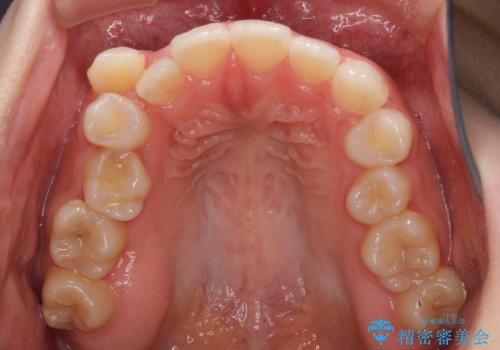

本来であれば八重歯の隣後方の歯を抜歯するのですが、その後ろの歯が乳歯であり後続永久歯もなかったため、乳歯を抜去することとしました。

前から5番目の乳歯は、後続永久歯である小臼歯と比べて幅径が大きいため、移動に時間がかかりましたが、きれいに仕上げることができました。